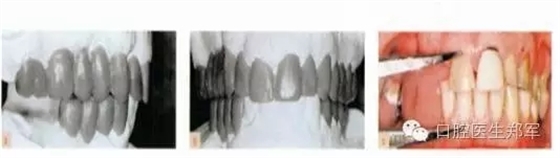

•診斷蠟型(圖6);

圖6 a-b 診斷蠟型 c 根據(jù)美學(xué)、生物力學(xué)和臨床冠高度的標(biāo)準(zhǔn),設(shè)計(jì)咬合垂直距離。 |

圖7治療計(jì)劃。后牙支撐:右側(cè)種植體支持式修復(fù)的相對上下牙段、左側(cè)為縮短的牙支持式修復(fù)的牙弓。少量增加咬合垂直距離,在前牙設(shè)計(jì)非正中引導(dǎo)和左右尖牙引導(dǎo)。 |